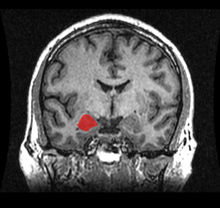

The amygdalae (singular: amygdala; /əˈmɪɡdələ/; also corpus amygdaloideum; Latin, from Greek ἀμυγδαλή, amygdalē, 'almond', 'tonsil'[1]) are two almond-shaped groups of nuclei located deep and medially within the temporal lobes of the brain in complex vertebrates, including humans.[2] Shown in research to perform a primary role in the processing of memory, decision-making, and emotional reactions, the amygdalae are considered part of the limbic system.[3]